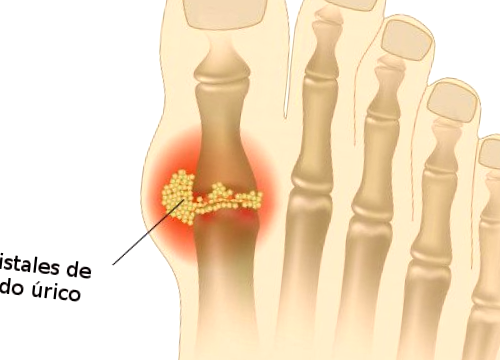

En definitiva, las causas que provocan este trastorno son muy diversas y es preciso controlarlas todas para que las desviaciones sean lo menos trascendentes posibles. Los niveles altos de ácido úrico no son fáciles de combatir, sin embargo tampoco resulta imposible rebajarlos y para ello es preciso realizar cambios sustanciales en nuestro día a día. Se trata de un proceso muy similar al de perder peso, que requiere constancia y esfuerzo diario. Muchas veces es necesario comenzar a notar los síntomas, como la dolorosa gota o los incómodos cálculos renales, para comenzar a actuar. Sin embargo, en dicho punto disminuir la tasa de urea en sangre será doblemente trabajoso y es preciso concienciar a la población de dicha situación.